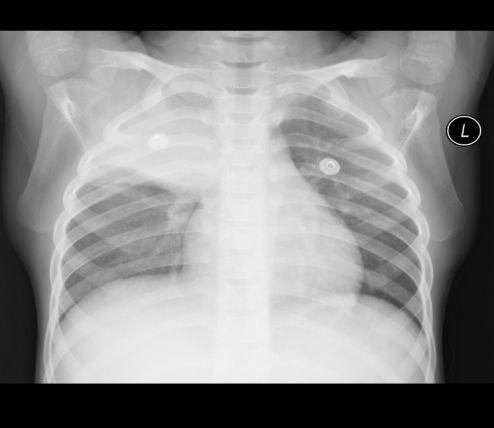

胸片爆料2025年最新版